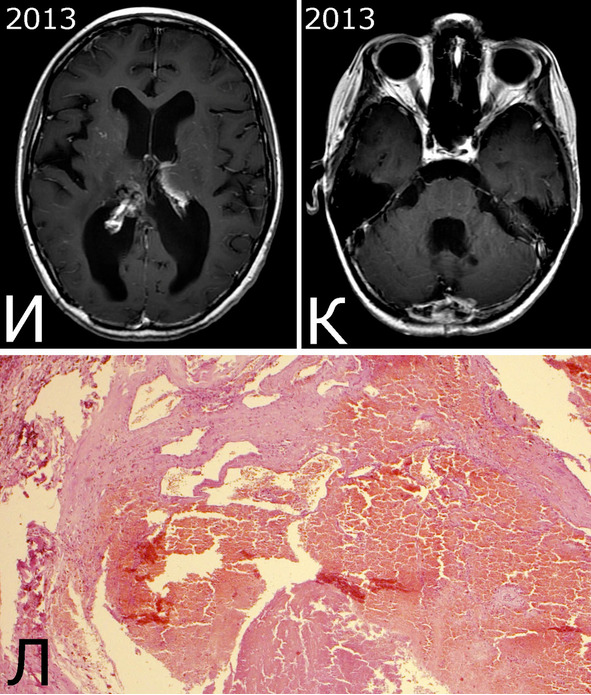

Рис. 28.III. Б-ная К-я, 1988 г. р. Радиоиндуцированная кавернозная мальформация и множественный дисангиогенез (?).

Анамнез (б-ная К-я, 1988 г. р.): в 2001 г (13 лет) обнаружена и удалена (субтотально) глиобластома задних отделов зрительного бугра справа. Проведен курс лучевой терапии. (А – МРТ до операции, режим Т2; Б – МРТ после операции и лучевой терапии, режим Т1). В августе 2002 г произведено радиохирургическое лечение оставшейся части опухоли. При последущих ежегодных обследованиях признаков продолженного роста опухоли не было (В – контрольная МРТ в 2008 г, режим Т1). Неврологического дефицита не было. С января 2011 г после падения на улице появилось пошатывание при ходьбе, которое через несколько месяцев регрессировало. При очередном контрольном обследовании в 2012 г выявлено объемное образование червя мозжечка, расцененное как хроническая гематома (Д, Е – МРТ, режимы Т2, Т1). Кроме того, в режиме SWAN обнаружено множество мелких очагов низкого сигнала, преимущественно перивентрикулярно, имеющих вид КМ IV типа (Ж, З – МРТ, режим SWAN). 01.11.2012 выполнена операция удаления гематомы: Поверхность червя мозжечка в средних его отделах резко изменена, желтого цвета и выбухает. Произведена коагуляция прилежащих участков коры и на глубине нескольких мм обнаружена капсула хронической гематомы. Капсула очень плотная. Она рассечена скальпелем. Содержимое ее – организовавшиеся кровяные сгустки. Помимо основной организовавшейся гематомы было еще несколько крупных полостей с такими же плотными стенками, заполненными кровяными сгустками. С передней части к упомянутому выше новообразованию подходили ветви мозжечковых артерий, которые коагулированы и пересечены. Основные стволы были смещены в сторону и сохранены. Постепенно путем кускования и иссечения фрагментов гематомы, по всей вероятности, и кавернозной мальформации, это новообразование удалено полностью. Оно было окружено измененной мозговой тканью желтого цвета. Ложе удаленной гематомы выложено гемостатической ватой. Образовалась больших размеров полость в пределах верхних и средних отделов червя и прилежащих отделов мозжечка. Гистологический диагноз: ткань мозжечка с капсулой гематомы с кровоизлияниями различной давности, скоплениями макрофагов и сидерофагов, очаговыми лимфоидными инфильтратами. В капсуле гематомы обнаружен микроскопический фрагмент кавернозной мальформации (Л – гистологический препарат, ув. Х 50). МРТ после операции – полное удаление гематомы (И, К – МРТ, режим Т1).